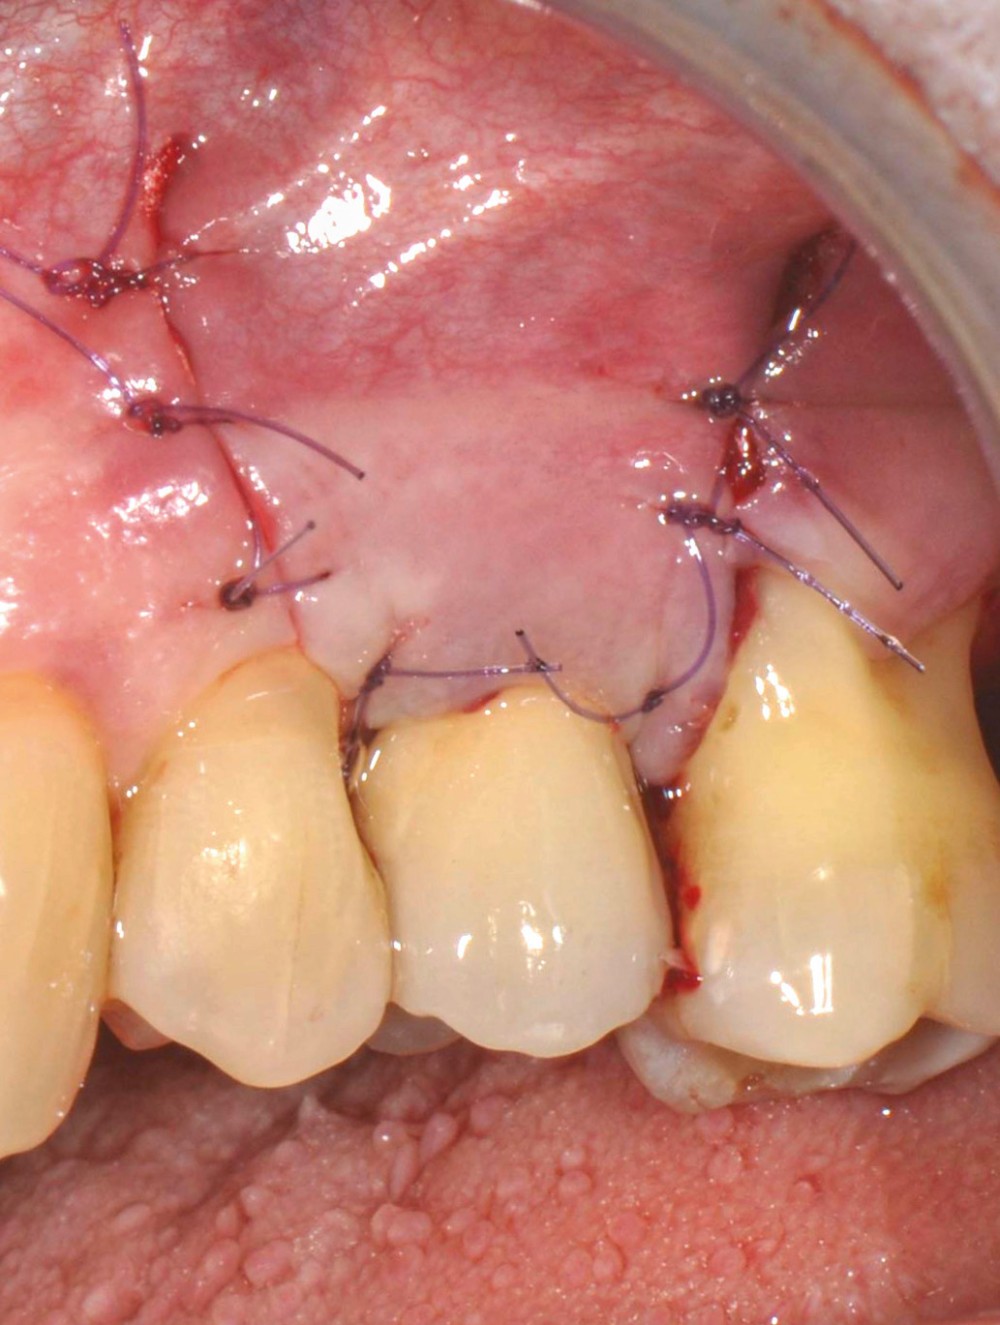

Chez cette patiente, le traitement de la péri-implantite a été réalisé à l’aide d’une technique de régénération osseuse guidée péri-implantaire, dont l’indication a été principalement motivée par la morphologie du défaut osseux. Au-delà de la maîtrise du geste chirurgical, le bon résultat obtenu à trois ans est intimement lié à sa coopération en termes de suivi et de contrôle de plaque.

13 et 14. À 3 ans, une régénération osseuse satisfaisante et un bel aspect des tissus péri-implantaires sont observés. Les poches font 3 mm en mésial, distal et palatin, et 2 mm en vestibulaire. Il n’y a pas de saignement au sondage.